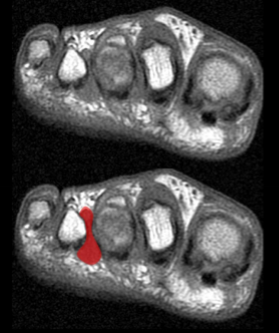

Morton’s neuroma